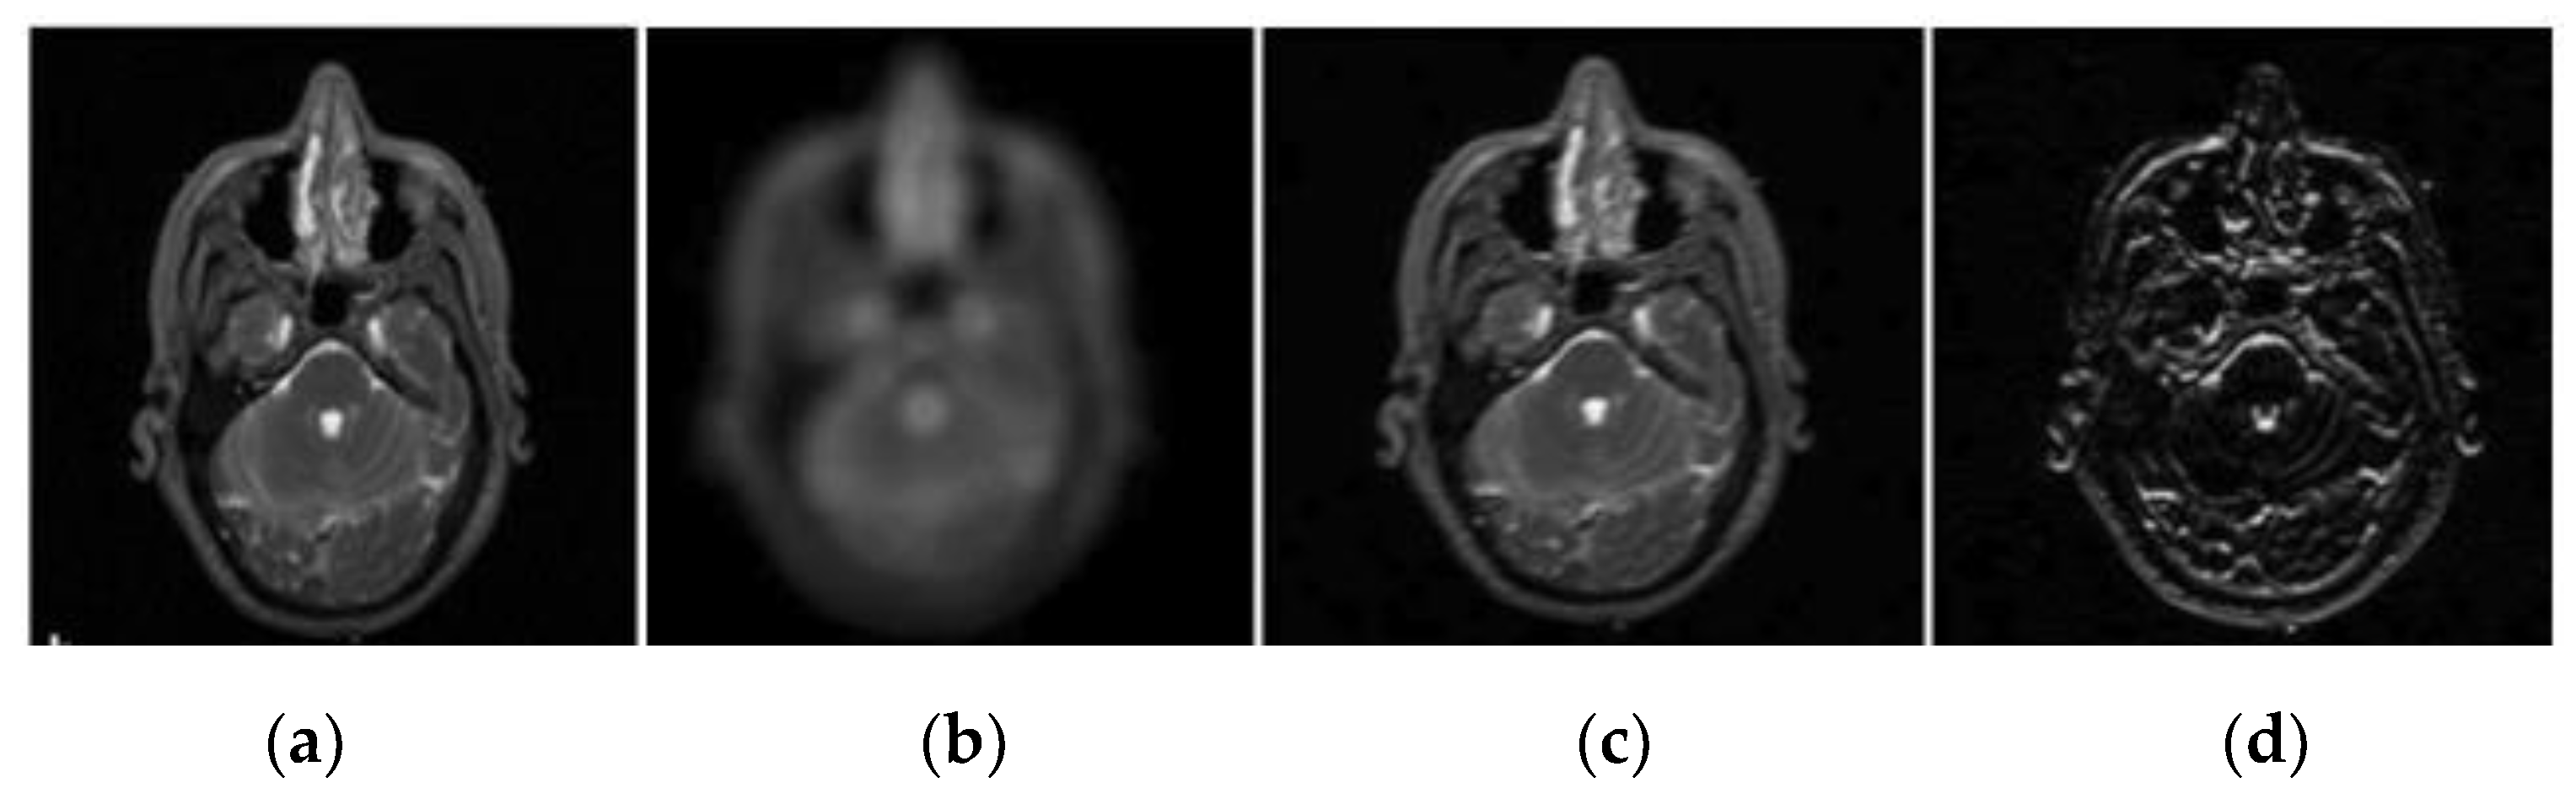

2.2. Wavelet Decomposition

2.3. Generation of Saliency Maps